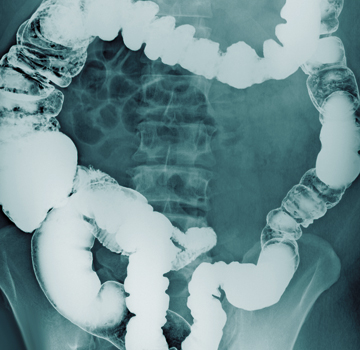

Intestinal obstruction

It is a blockage that completely prevents or significantly alters the transit of intestinal content. The most common causes in adults are scar tissue from previous abdominal surgery, hernias, and tumors. The diagnosis is based on the results of the physical and radiological examination.

Symptoms: Severe abdominal pain, vomiting, bloating, strong gas, bloating, inability to pass gas, constipation, for frequent treatment.